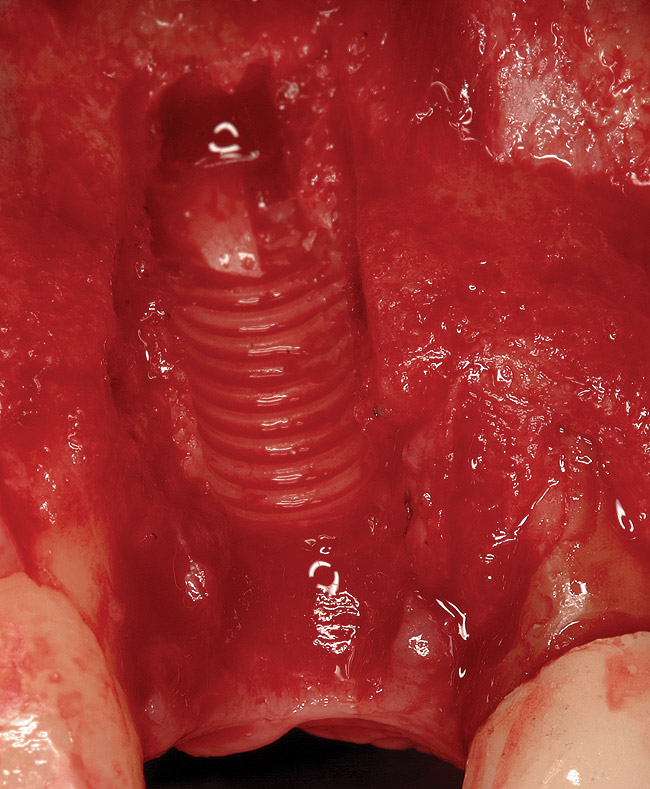

Figure 2  (Case 1) Condition of implant at surgical exposure.

Figure 2

Figure 3  (Case 1) Removal of implant was accomplished using piezo-surgery in order to maintain the lingual plate. Note that trephines are not recommended for this procedure.

Figure 3